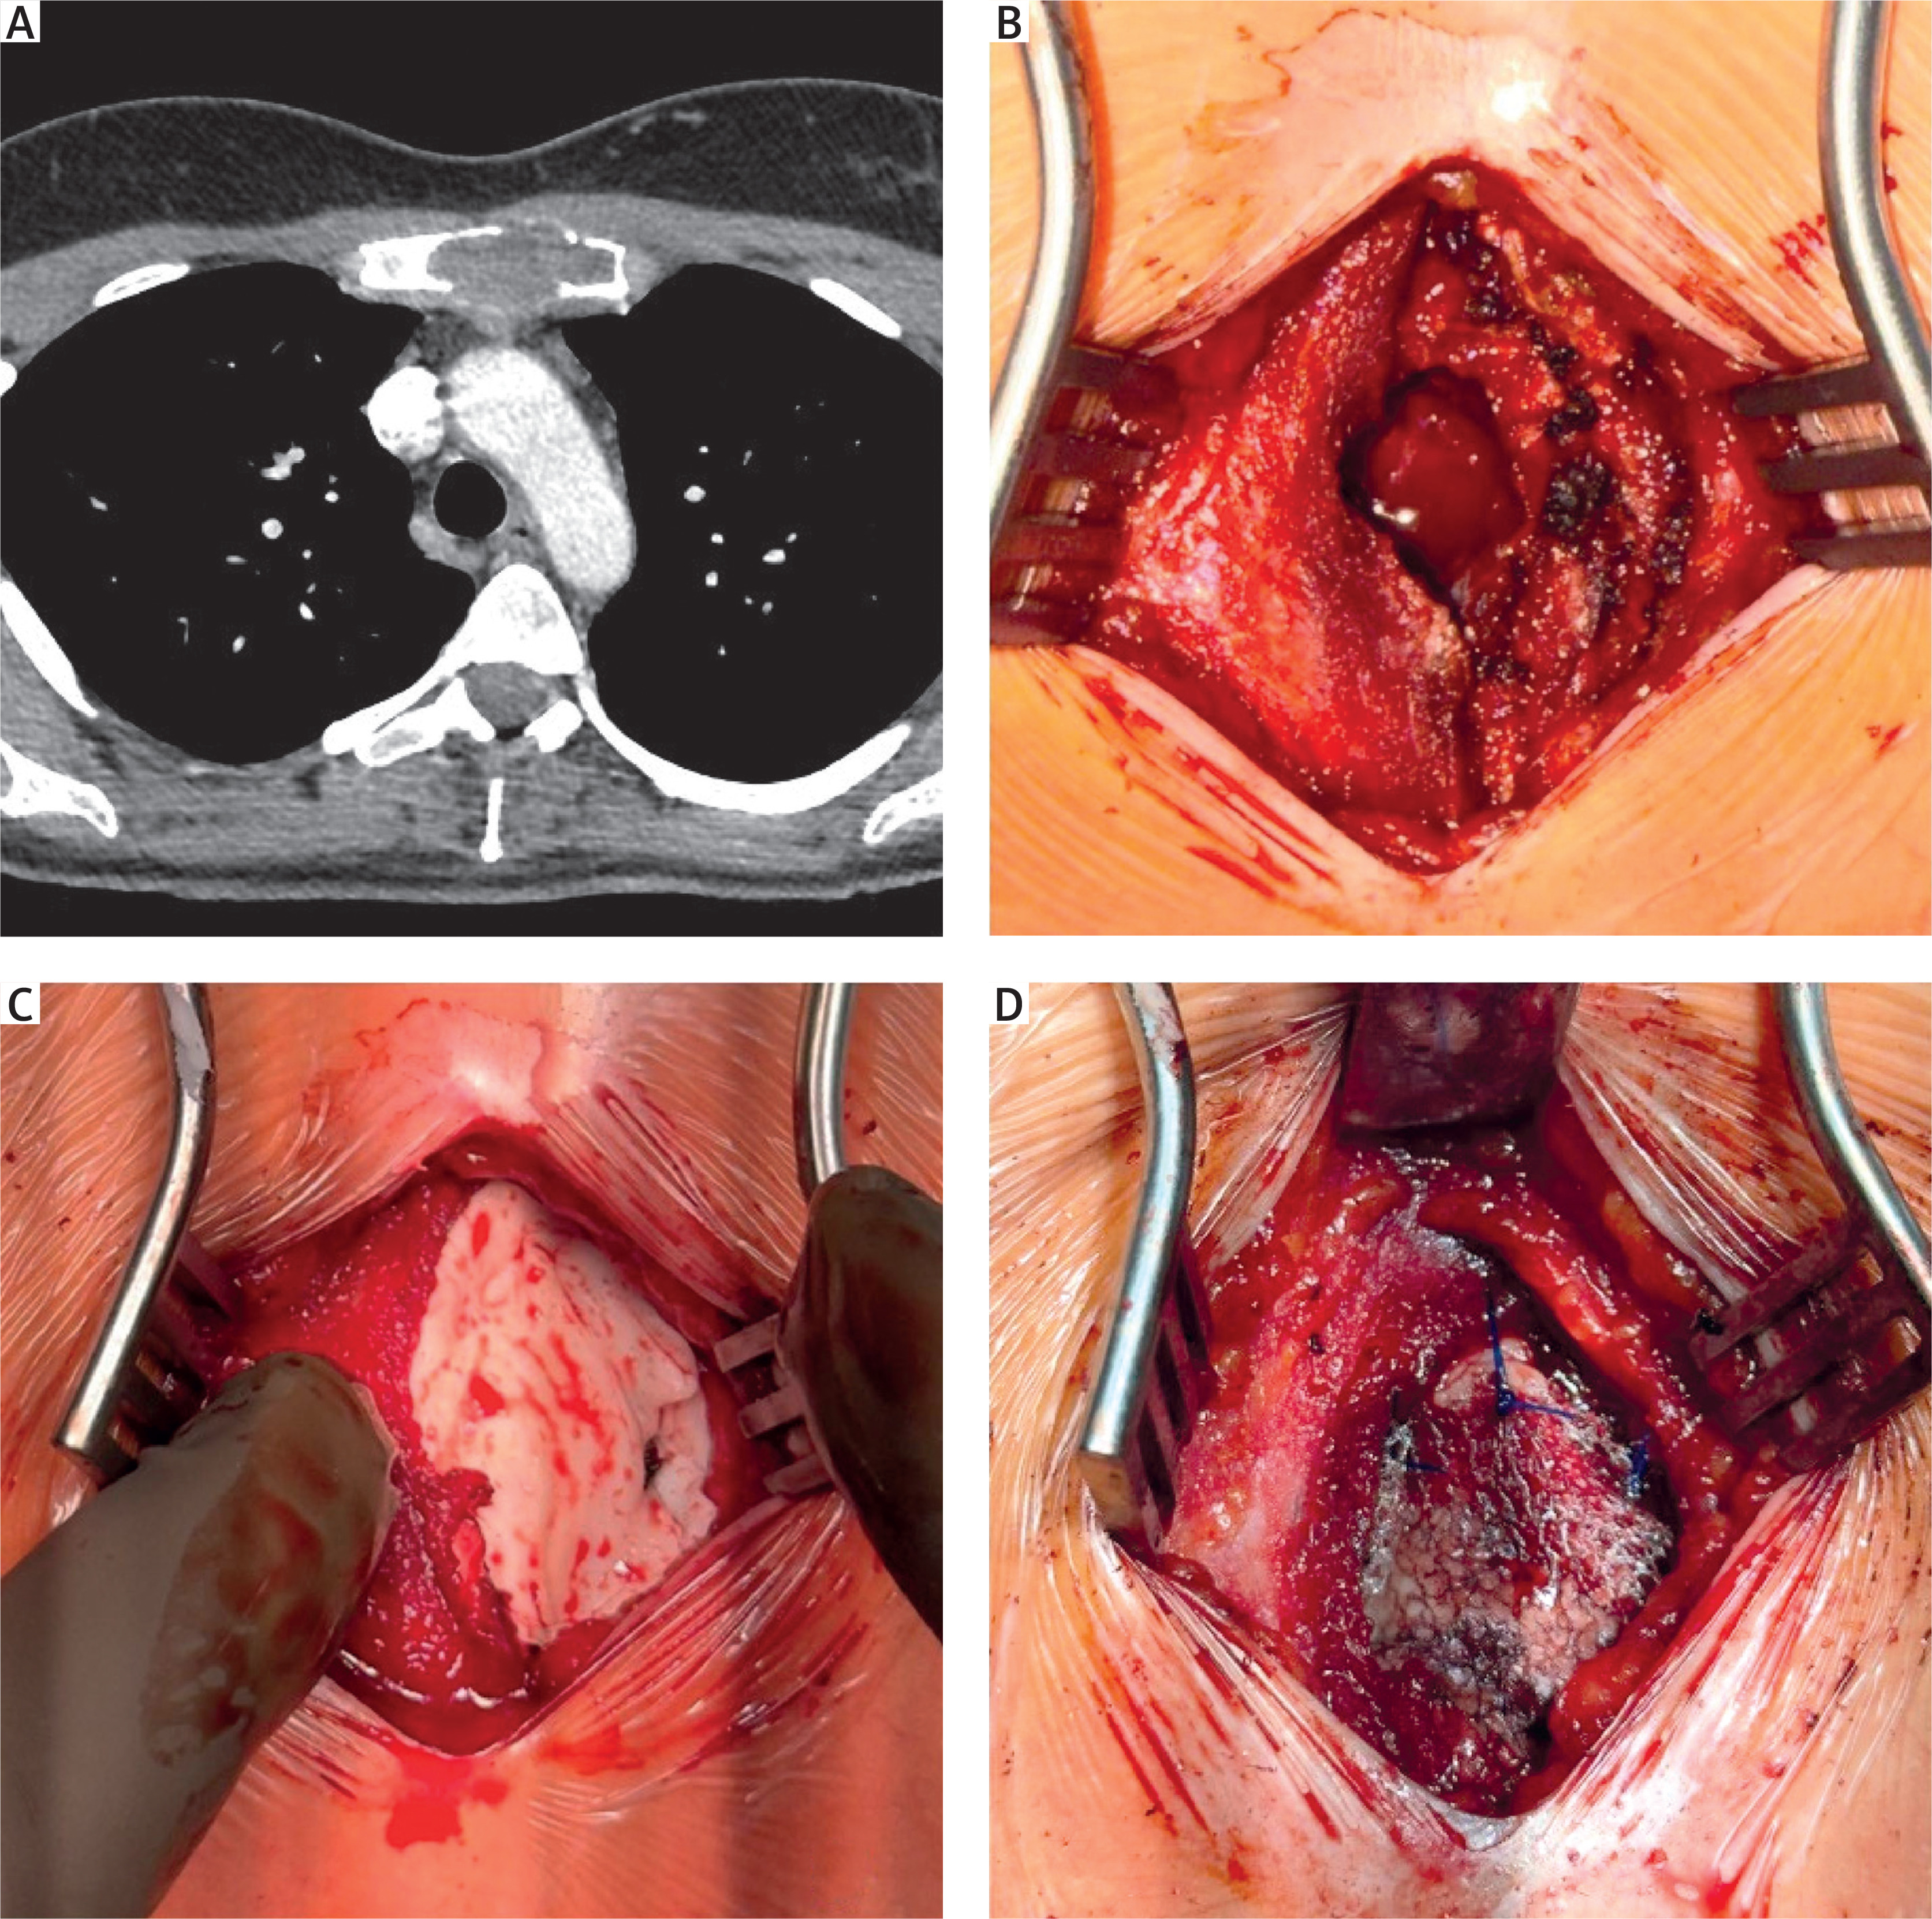

Figure 1

Radiological and intraoperative images. A – Chest computed tomography (CT) scan showing a lesion in the manubrium sterni. B – Intraoperative view of the anterior plate of the sternum with a bone defect. C – Cavity filled with surgical cement mixed with gentamicin. D – Anterior surface of the sternum covered with a mesh fixed with sutures

Under general anesthesia, a midline incision over the manubrium sterni was made. Following dissection, a small anterior cortical defect was noted (Figure 1 B). The cortical defect was enlarged, and the pathologically altered marrow cavity was curetted. The material was sent for histopathological analysis. A mesh was introduced into the bottom of the cavity, followed by surgical cement mixed with gentamicin, filling the cavity (Figure 1 C). A mesh was applied to the anterior surface of the sternum, covering the bone defect. The mesh was secured with simple sutures (Figure 1 D). The wound was closed with sutures, and a sterile dressing was applied. Postoperatively, the patient was transferred to the recovery ward and received analgesic treatment. The procedure was uneventful.